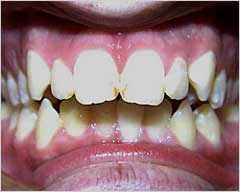

هي حاله بسيطه قبل وبعد للتقدم بسيط او بروز في الفك العلوي